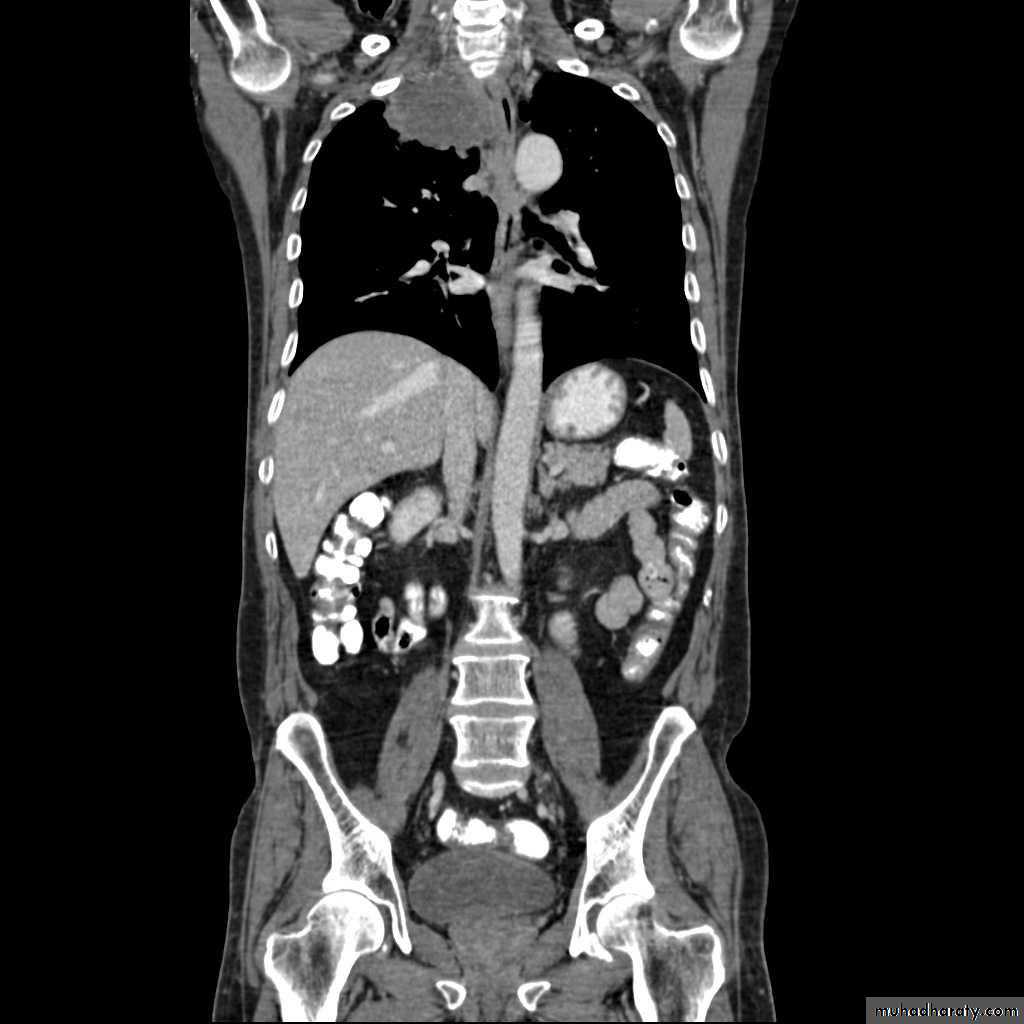

Hydatid cysts result from infection by the Echinococcus, and can result in cyst formation anywhere in the body. Humans are accidental host and the infection occurs by ingesting food contaminated with Echinococcus eggs ,Pulmonary hydatid infection is a common manifestation of hydatid disease.The lung is the second most common site of involvement with echinococcosis granulosus in adults after the liver (10-30% of cases), and the most common site in children. The coexistence of liver and lung disease is present in only 6% of patients .

Chest XR features include :

Non-complicated hydatid

multiple or solitary rounded opacity

diameter of 1-20 cm

unilateral or bilateral

predominantly found in the lower lobes

Complicated cysts may show:

meniscus sign or air crescent sign

cumbo sign or onion peel signThe onion peel sign (also called the cumbo sign) is a feature seen with complicated pulmonary hydatid cyst in which air lining between the endocyst and pericyst has the appearance of an onion

water-lily is seen in hydatid infections when there is detachment of the endocyst membrane which results in floating membranes within the pericyst that mimic the appearance of a water lily.

consolidation adjacent to the cyst (ruptured cyst)